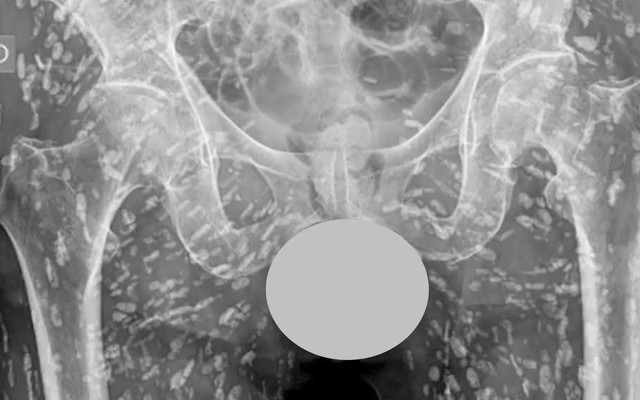

‘Phát hoảng’ với ảnh chụp X-quang chi chít đốm trắng dọc cơ thể: Bác sĩ chỉ đích danh thủ phạm

Sống khỏe 2025-05-09T10:01:00Gần đây, trên mạng xã hội lan truyền ảnh chụp X-quang của một bệnh nhân với chi chít đốm trắng trong cơ thể. Hình ảnh này khiến nhiều người cảm thấy bàng hoàng.